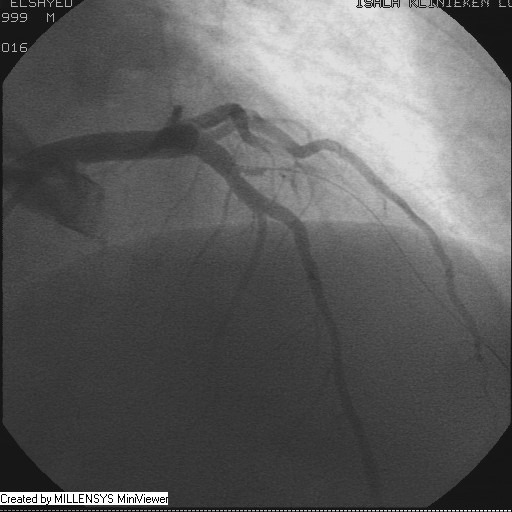

Patient transfered to Cardiac Catheterization Laboratory, coronary angiography showed atherosclerotic coronaries but without significant lesions, especially LAD that was patent with TIMI 3 flow (Figure 1- 5). Re-evaluation of the Angiography showed a small stump that can be for an occluded 1st diagonal (Figure 2a), at that level the LAD has a non-significant lesion.

Figure 3

Figure 4

Figure 5